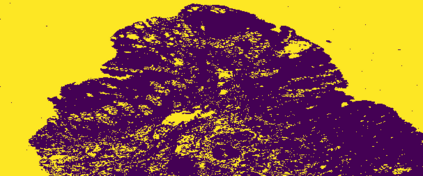

The usage of chemical imaging technologies is becoming a routine accompaniment to traditional methods in pathology. Significant technological advances have developed these next generation techniques to provide rich, spatially resolved, multidimensional chemical images. The rise of digital pathology has significantly enhanced the synergy of these imaging modalities with optical microscopy and immunohistochemistry, enhancing our understanding of the biological mechanisms and progression of diseases. Techniques such as imaging mass cytometry provide labelled multidimensional (multiplex) images of specific components used in conjunction with digital pathology techniques. These powerful techniques generate a wealth of high dimensional data that create significant challenges in data analysis. Unsupervised methods such as clustering are an attractive way to analyse these data, however, they require the selection of parameters such as the number of clusters. Here we propose a methodology to estimate the number of clusters in an automatic data-driven manner using a deep sparse autoencoder to embed the data into a lower dimensional space. We compute the density of regions in the embedded space, the majority of which are empty, enabling the high density regions to be detected as outliers and provide an estimate for the number of clusters. This framework provides a fully unsupervised and data-driven method to analyse multidimensional data. In this work we demonstrate our method using 45 multiplex imaging mass cytometry datasets. Moreover, our model is trained using only one of the datasets and the learned embedding is applied to the remaining 44 images providing an efficient process for data analysis. Finally, we demonstrate the high computational efficiency of our method which is two orders of magnitude faster than estimating via computing the sum squared distances as a function of cluster number.